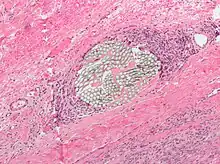

Surgical suture. H&E stain.

Splinters are common foreign bodies in skin. Staphylococcus aureus infection often causes boils to form around them.[11]